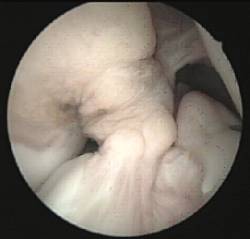

Existeix, així mateix, la possibilitat de lesions parcials del lligament creuat en què només es trobi afectat un dels seus fascicles (anteromedial o posterolateral).

Quan l’afectació determina la presència de simptomatologia clínica s’aconsella la reparació selectiva del fascicle lesionat mitjançant ligamentoplàsties de reforç artroscòpiques preservant les restes de lligament creuat anterior funcionants